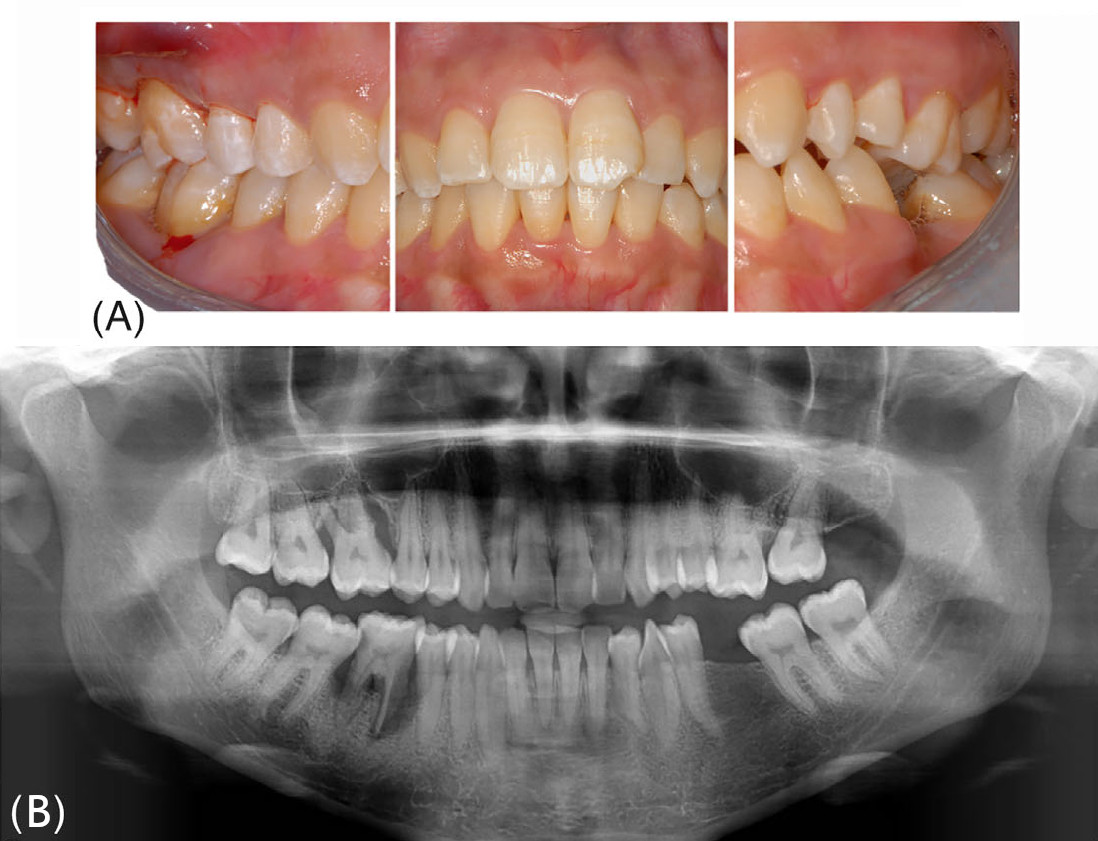

В мае 2022 года в отделение стоматологии AUSL г. Феррары (Италия) обратилась 24-летняя пациентка для пародонтологической консультации. Основные жалобы были связаны с подвижностью зубов и постоянной болью (усиливающейся при жевании) в правых дистальных секстантах. В анамнезе — самопроизвольное выпадение левого нижнего первого моляра; пациентка выразила желание сохранить оставшиеся зубы. После полного пародонтологического обследования пациентке был поставлен диагноз «пародонтит стадии III, степени C, паттерн «резцы-моляры». Высокий риск прогрессирования пародонтита был рассчитан с помощью метода PerioRisk. Индексы зубного налёта (FMPS) и кровоточивости (FMBS) составили 80% и 76% соответственно.

Фото 1. Клиническая картина при первом визите. (A) Вид в полости рта; (B) Панорамная рентгенограмма

Отсутствие пародонтологической стабильности и высокий уровень риска по PerioRisk сохранялись после II этапа терапии, главным образом вследствие глубоких (>6 мм) остаточных кровоточащих карманов и выраженной рентгенологической потери костной ткани (около 90% длины корня) у правых верхнего и нижнего первых моляров (16 и 46). Сопутствующее наличие фуркационных поражений III класса и подвижности III степени дополнительно осложняло прогноз двух указанных моляров, которые были признаны зубами с безнадёжным прогнозом согласно Квоку и Кэтону и запланированы к удалению. После трёхмерного рентгенологического исследования методом конусно-лучевой компьютерной томографии в числе доступных вариантов замещения была выбрана АТЗ правых третьих моляров (18 и 48) на позиции 16 и 46 соответственно. Оба донорских зуба имели полностью сформированные корни (IV стадия развития корня), правильно прорезались и были окружены альвеолярной костью на 90–100% длины своего корневого комплекса. Длина корня и мезиодистальная ширина коронки были расценены как совместимые с размерами реципиентных участков.